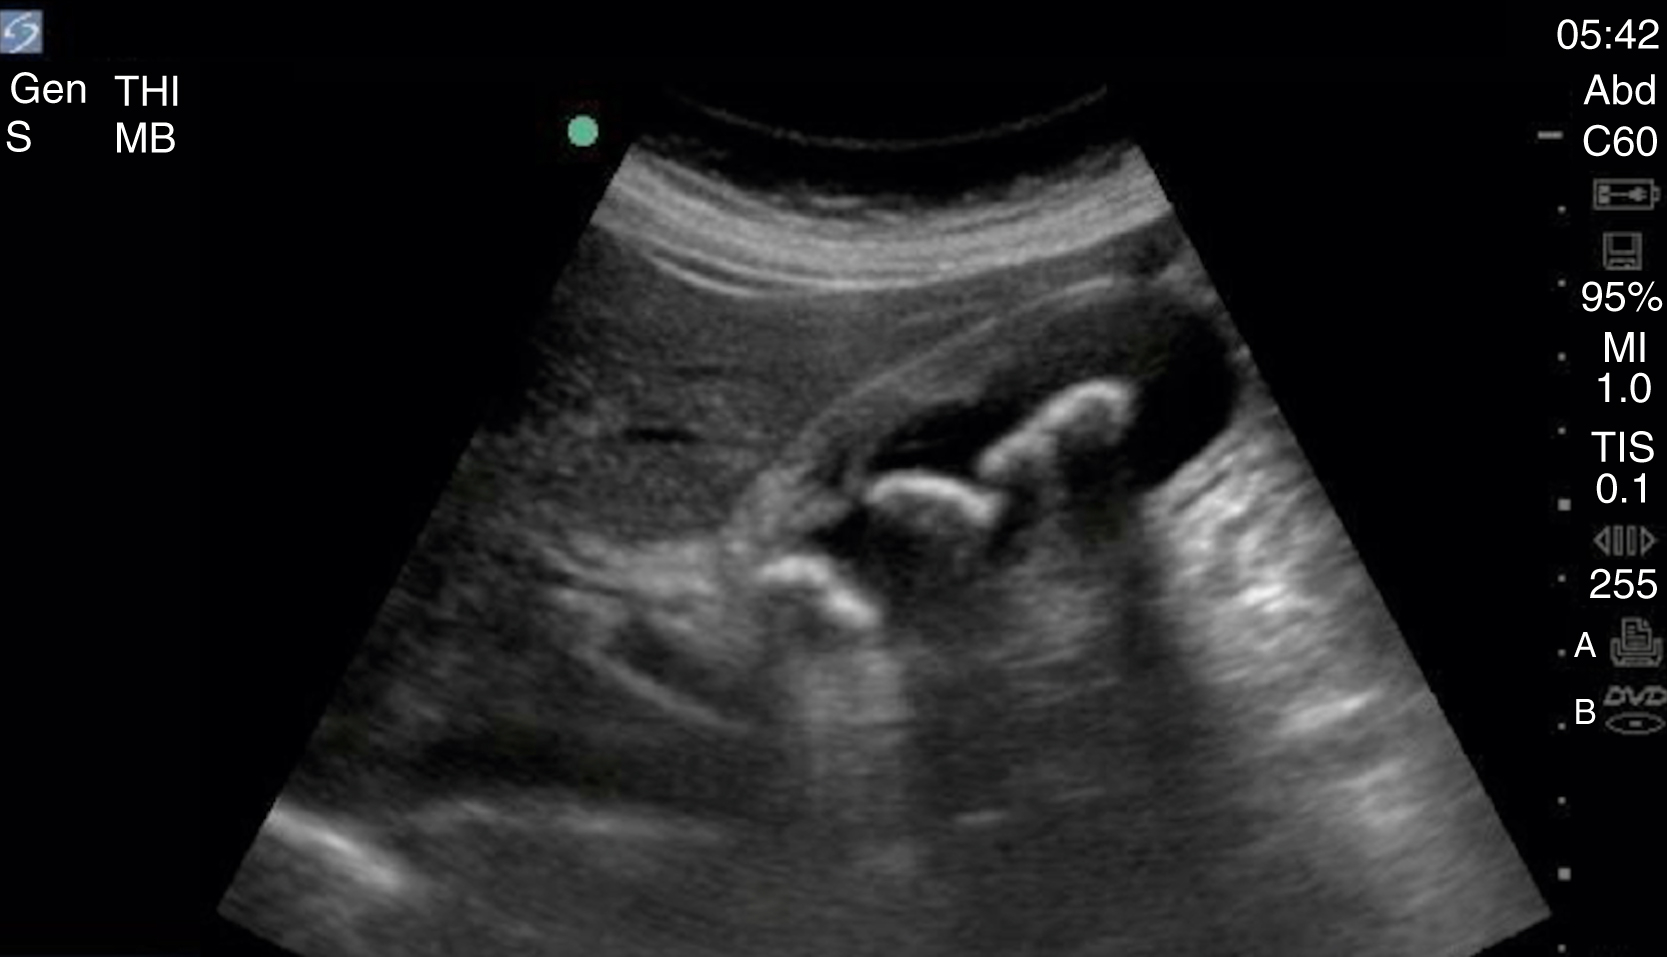

The diagnosis of cholelithiasis is made by identification of echogenic foci within the gallbladder lumen with associated shadowing. Other image patterns include stones with indistinct shadow, sludge, and the wall-echo-shadow (WES) sign seen in a gallbladder full of gallstones ( Video e3.5 ). Although many sonographic findings can be seen with AC, including gallstones, dilated gallbladder, increased gallbladder wall thickness (>3 mm), sonographic Murphy sign, pericholecystic fluid, and CBD dilatation, gallstones are present in 95% to 99% of AC cases ( Fig. e3.4 ). A nonmobile stone in the gallbladder neck, confirmed in the left lateral decubitus position, is highly suggestive of eventual cholecystitis. A CBD larger than 6 mm in people younger than 60 years and larger than 10 mm in older patients may indicate choledocholithiasis.

Sagittal gallbladder with signs of acute cholecystitis including stones with posterior shadowing, thickening of the wall anteriorly, and pericholecystic fluid seen within the wall of the gallbladder.